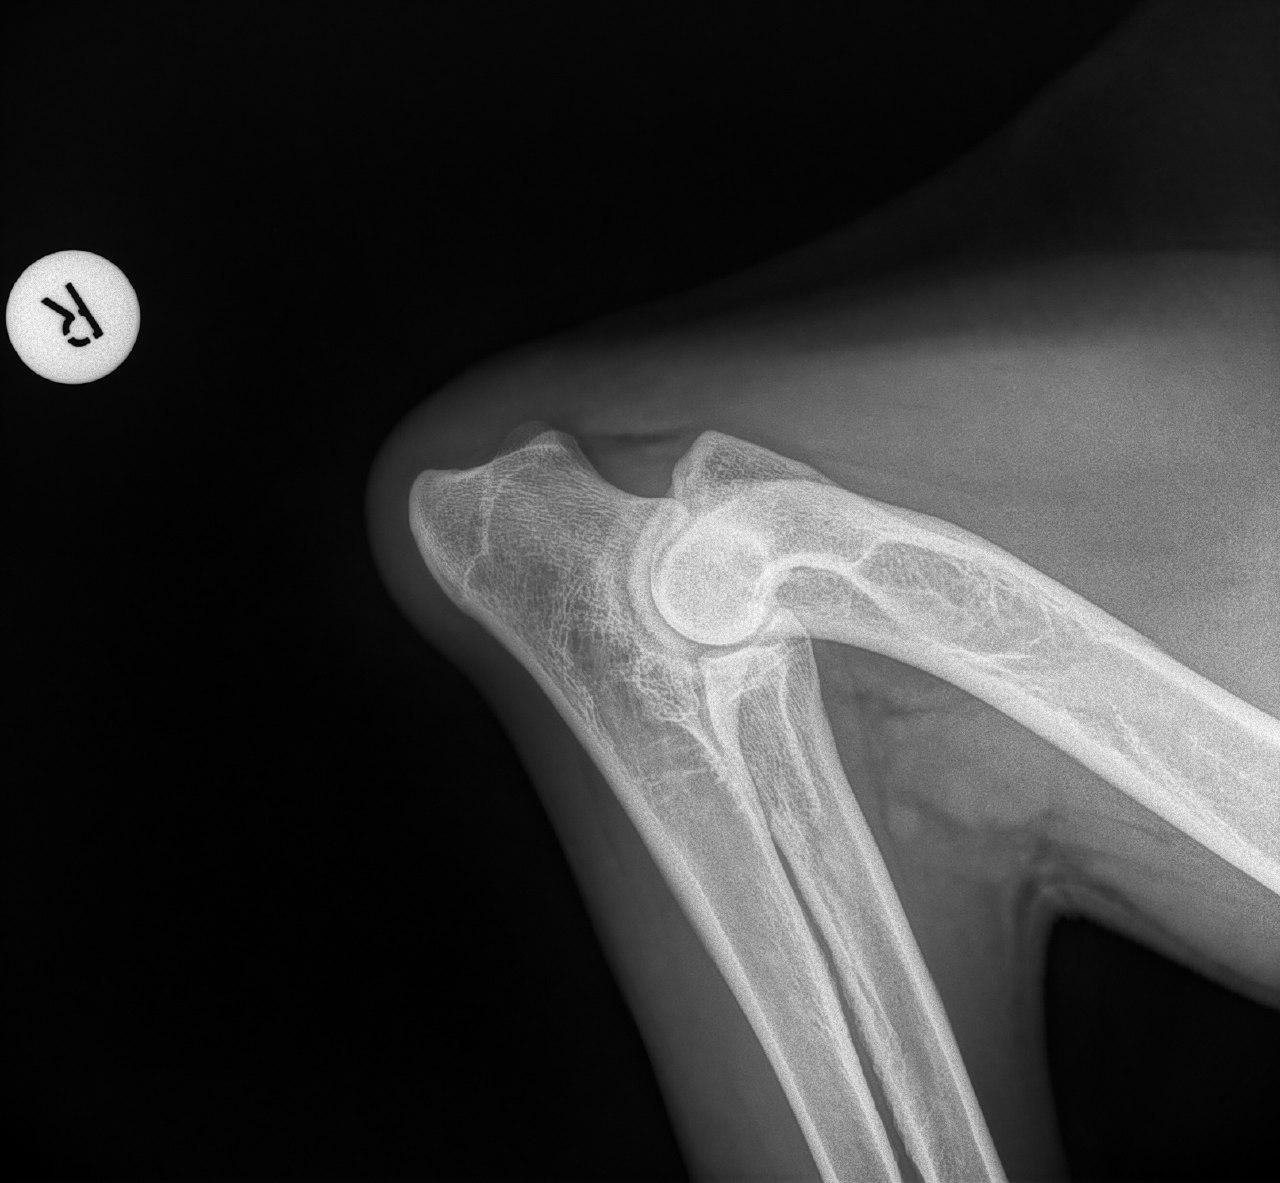

Mit der HD ist das so ne Sache..... die Vererbung spielt eine sehr große Rolle, ja. Aber bei unserer Peggy Zb ist es so, dass mehrere Generationen nachweislich HD und ED frei sind und auch frei von Spondylosen. Als einziger Hund überhaupt in der gesamten Zucht hat unsere Dame alles mitgenommen, was zu kriegen war;(: sie hat nicht nur schwere HD, weil ihre Hüfte viel zu locker ist, sondern dadurch bedingt am rechten Knie bereits schwere Arthrose und hinten links eine Sehenschwäche (durch Überlastung), weshalb sie dort durchtrittig ist. Und als würde das alles nicht schon vollkommen reichen, wurden aktuell auch noch mehrere heftige Spondylosen diagnostiziert;(. An einer Stelle ist sogar schon etwas abgebrochen8|.